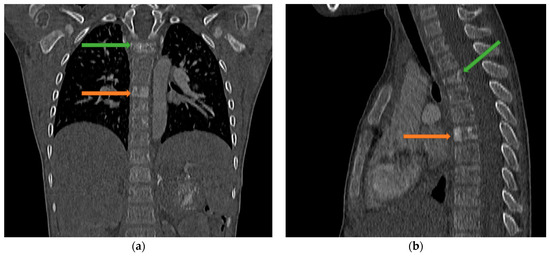

4. Case Presentation

5.3. Imaging